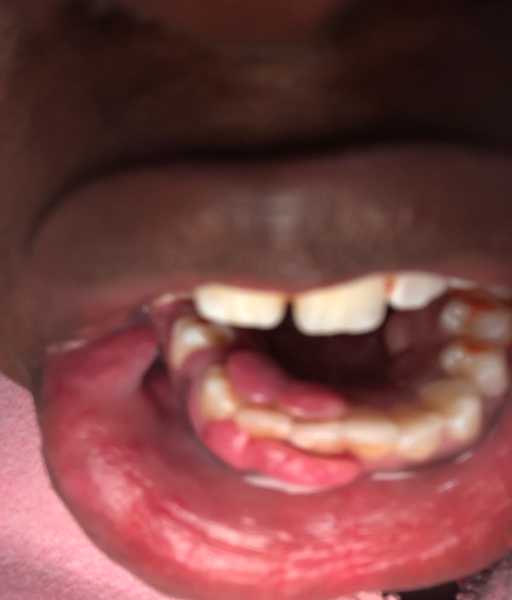

My gum is growing over my teeth

Why are my gums growing over my bottom teeth? It hurts so bad I can barely take it. I have a very hard time brushing because they bleed.They also bleed, it hurts when I eat. Sometimes I wake up in the middle of the night and have blood on my pillows or I spit out blood. I had surgery once before but it grew back please help me

Your gums are extrememly inflamed and infected.  I can see in the photo you submitted that there is a large amount of buildup (deposits) on your surrounding teeth as a result of poor oral hygiene.  You need to brush your teeth and massage your gums with the tooth brush to stimulate them.  Take an over-the-counter anti-inflammatory (Motrin or Advil) to help with the pain and inflammation.  Warm salt water rinses can help soothe the area.  Be sure you are flossing, you may have something lodged in the area such as a seed, nut or kernal.  Schedule an appointment with your dentist as soon as possible.  Laser tissue removal may result as the inflammation is extreme and almost an obstruction to your bite.